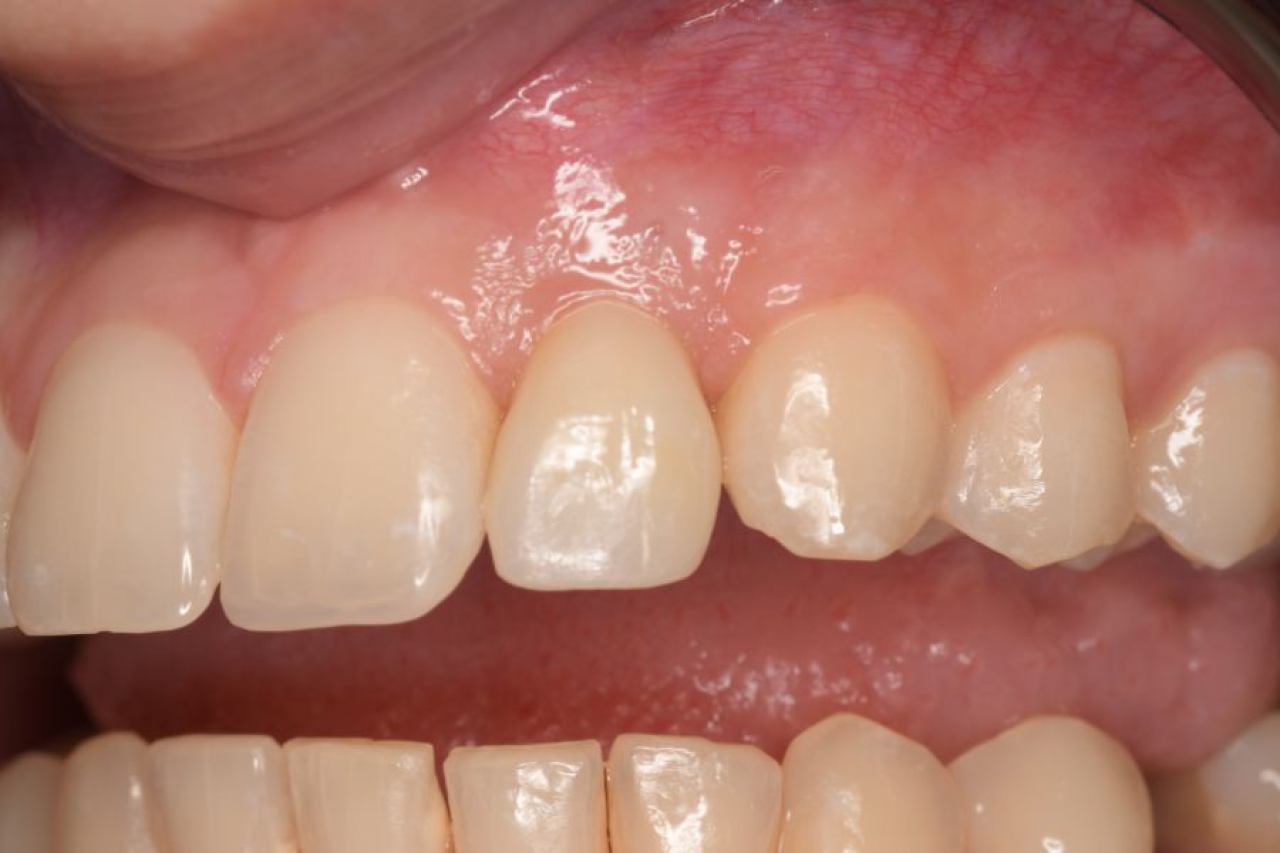

Regeneracija kosti i mekog tkiva

Gingivalne recesije u narodu poznatije kao „povlačenje zubnog mesa" moguće je korigirati kirurškim zahvatom te vratiti gingivu (zubno meso) u fiziološki položaj mikrokirurškim tehnikama. Zahvati koje odrađujemo kod regeneracije kosti i mekog tkiva su podizanje dna sinusa (sinus lift) i nadomještanje izgubljenog volumena kosti (augmentacija kosti, regeneracija kosti).